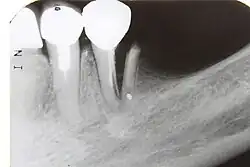

Im Verlauf einer odontogenen Infektion stirbt unbehandelt die Pulpa ab und die Keime breiten sich im System der Wurzelkanäle aus. Der Körper reagiert mit einer Entzündung des Zahnhalteapparates (Parodontitis apicalis) im Sinne einer Abwehrreaktion. Eine Parodontitis apicalis kann in einer akuten oder einer chronischen Form vorliegen. Die akute Form ist oft mit Schmerzen verbunden, sie kann unter Umständen röntgenologisch nur schwer verifiziert werden, während eine chronische Parodontitis apicalis bei einer Auflösung der Knochenstruktur im Bereich der Wurzelspitze im Röntgenbild als Aufhellung sichtbar sein kann. Im Röntgenbild erscheint die Aufhellung dunkel, da das Röntgenbild ein Negativ darstellt.

Der Ablauf einer Wurzelkanalbehandlung am Zahn 17

-

Röntgenaufnahme vor Wurzelkanalbehandlung -

Kontrollaufnahme nach Wurzelkanalbehandlung -

Kontrollaufnahme nach 20 Monaten